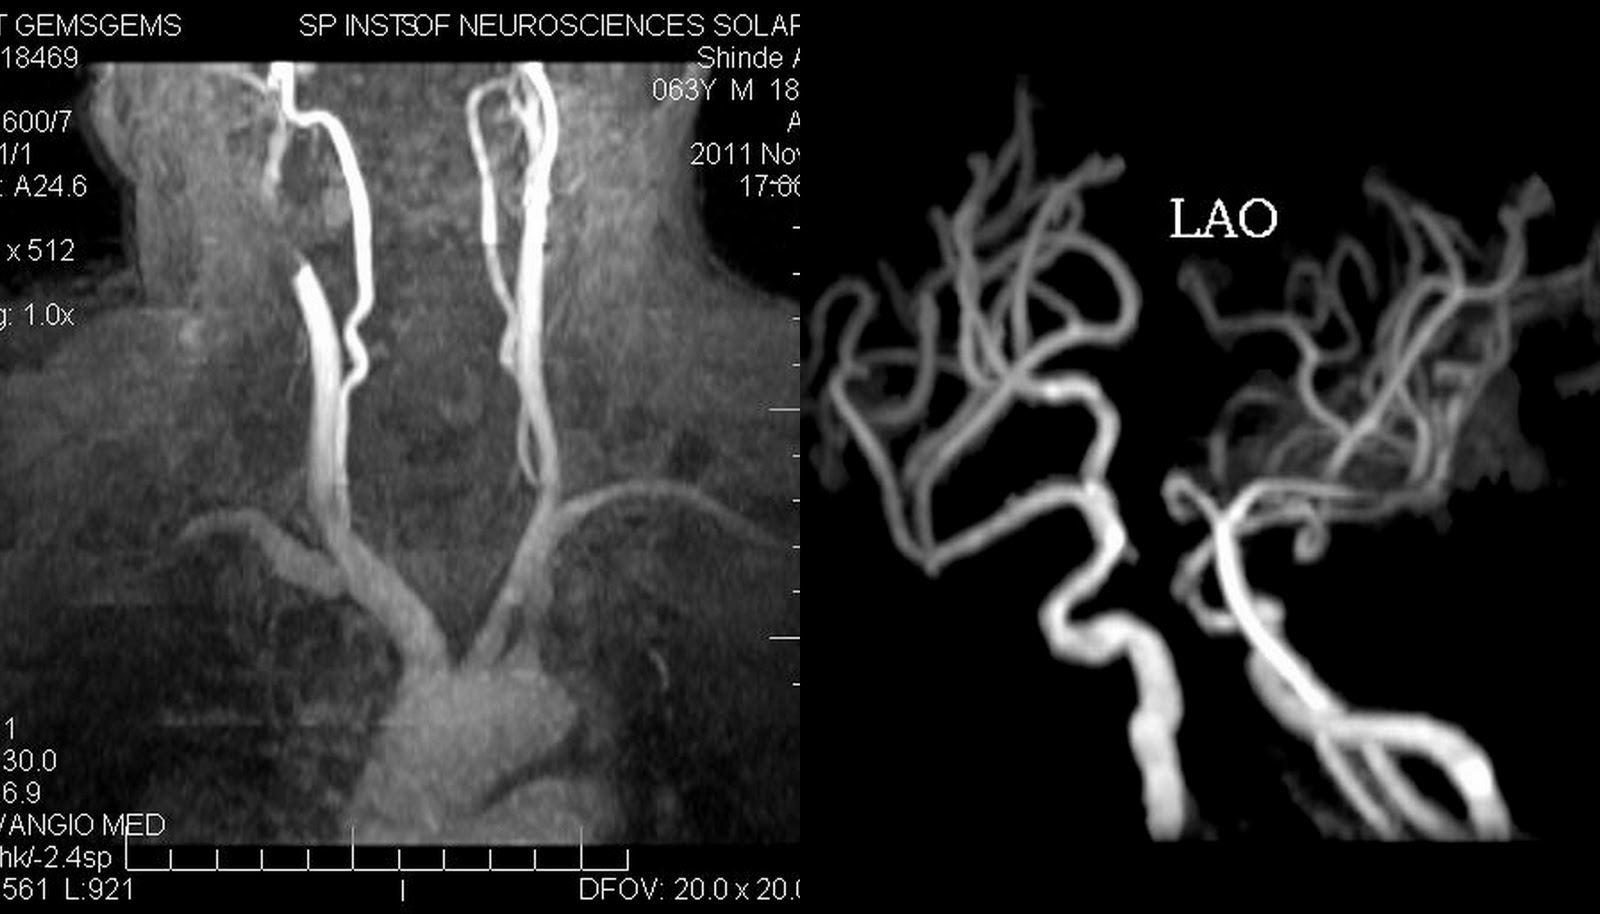

From www.neuroradiologycases.com